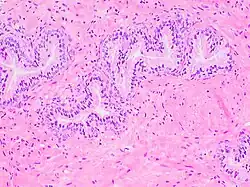

The prostate consists of glandular and connective tissue.[2] Tall column-shaped cells form the lining (the epithelium) of the glands.[2] These form one layer or may be pseudostratified.[4] The epithelium is highly variable and areas of low cuboidal or flat cells can also be present, with transitional epithelium in the outer regions of the longer ducts.[10] Basal cells surround the luminal epithelial cells in benign glands. The glands are formed as many follicles, which drain into canals and subsequently 12–20 main ducts, These in turn drain into the urethra as it passes through the prostate.[4] There are also a small amount of flat cells, which sit next to the basement membranes of glands, and act as stem cells.[2]

The connective tissue of the prostate is made up of fibrous tissue and smooth muscle.[2] The fibrous tissue separates the gland into lobules.[2] It also sits between the glands and is composed of randomly orientated smooth-muscle bundles that are continuous with the bladder.[11]

Microscopic glands of the prostate -

Microanatomy of a prostatic gland, showing both luminal cells and surrounding basal cells. H&E stain. -

Histology of normal prostate, H&E stain, with benign features: Glands are rounded to irregularly branching, with an inner layer of epithelial cells surrounded by an outer layer of basal cells. They are surrounded by ample stroma. -

Histology of prostate with gradually increasing simple atrophy from left to right, H&E stain. Crowding and angulation may mimic that of adenocarcinoma, but there is nuclear basophilia rather than atypia, and occasional basal cells can still be seen.